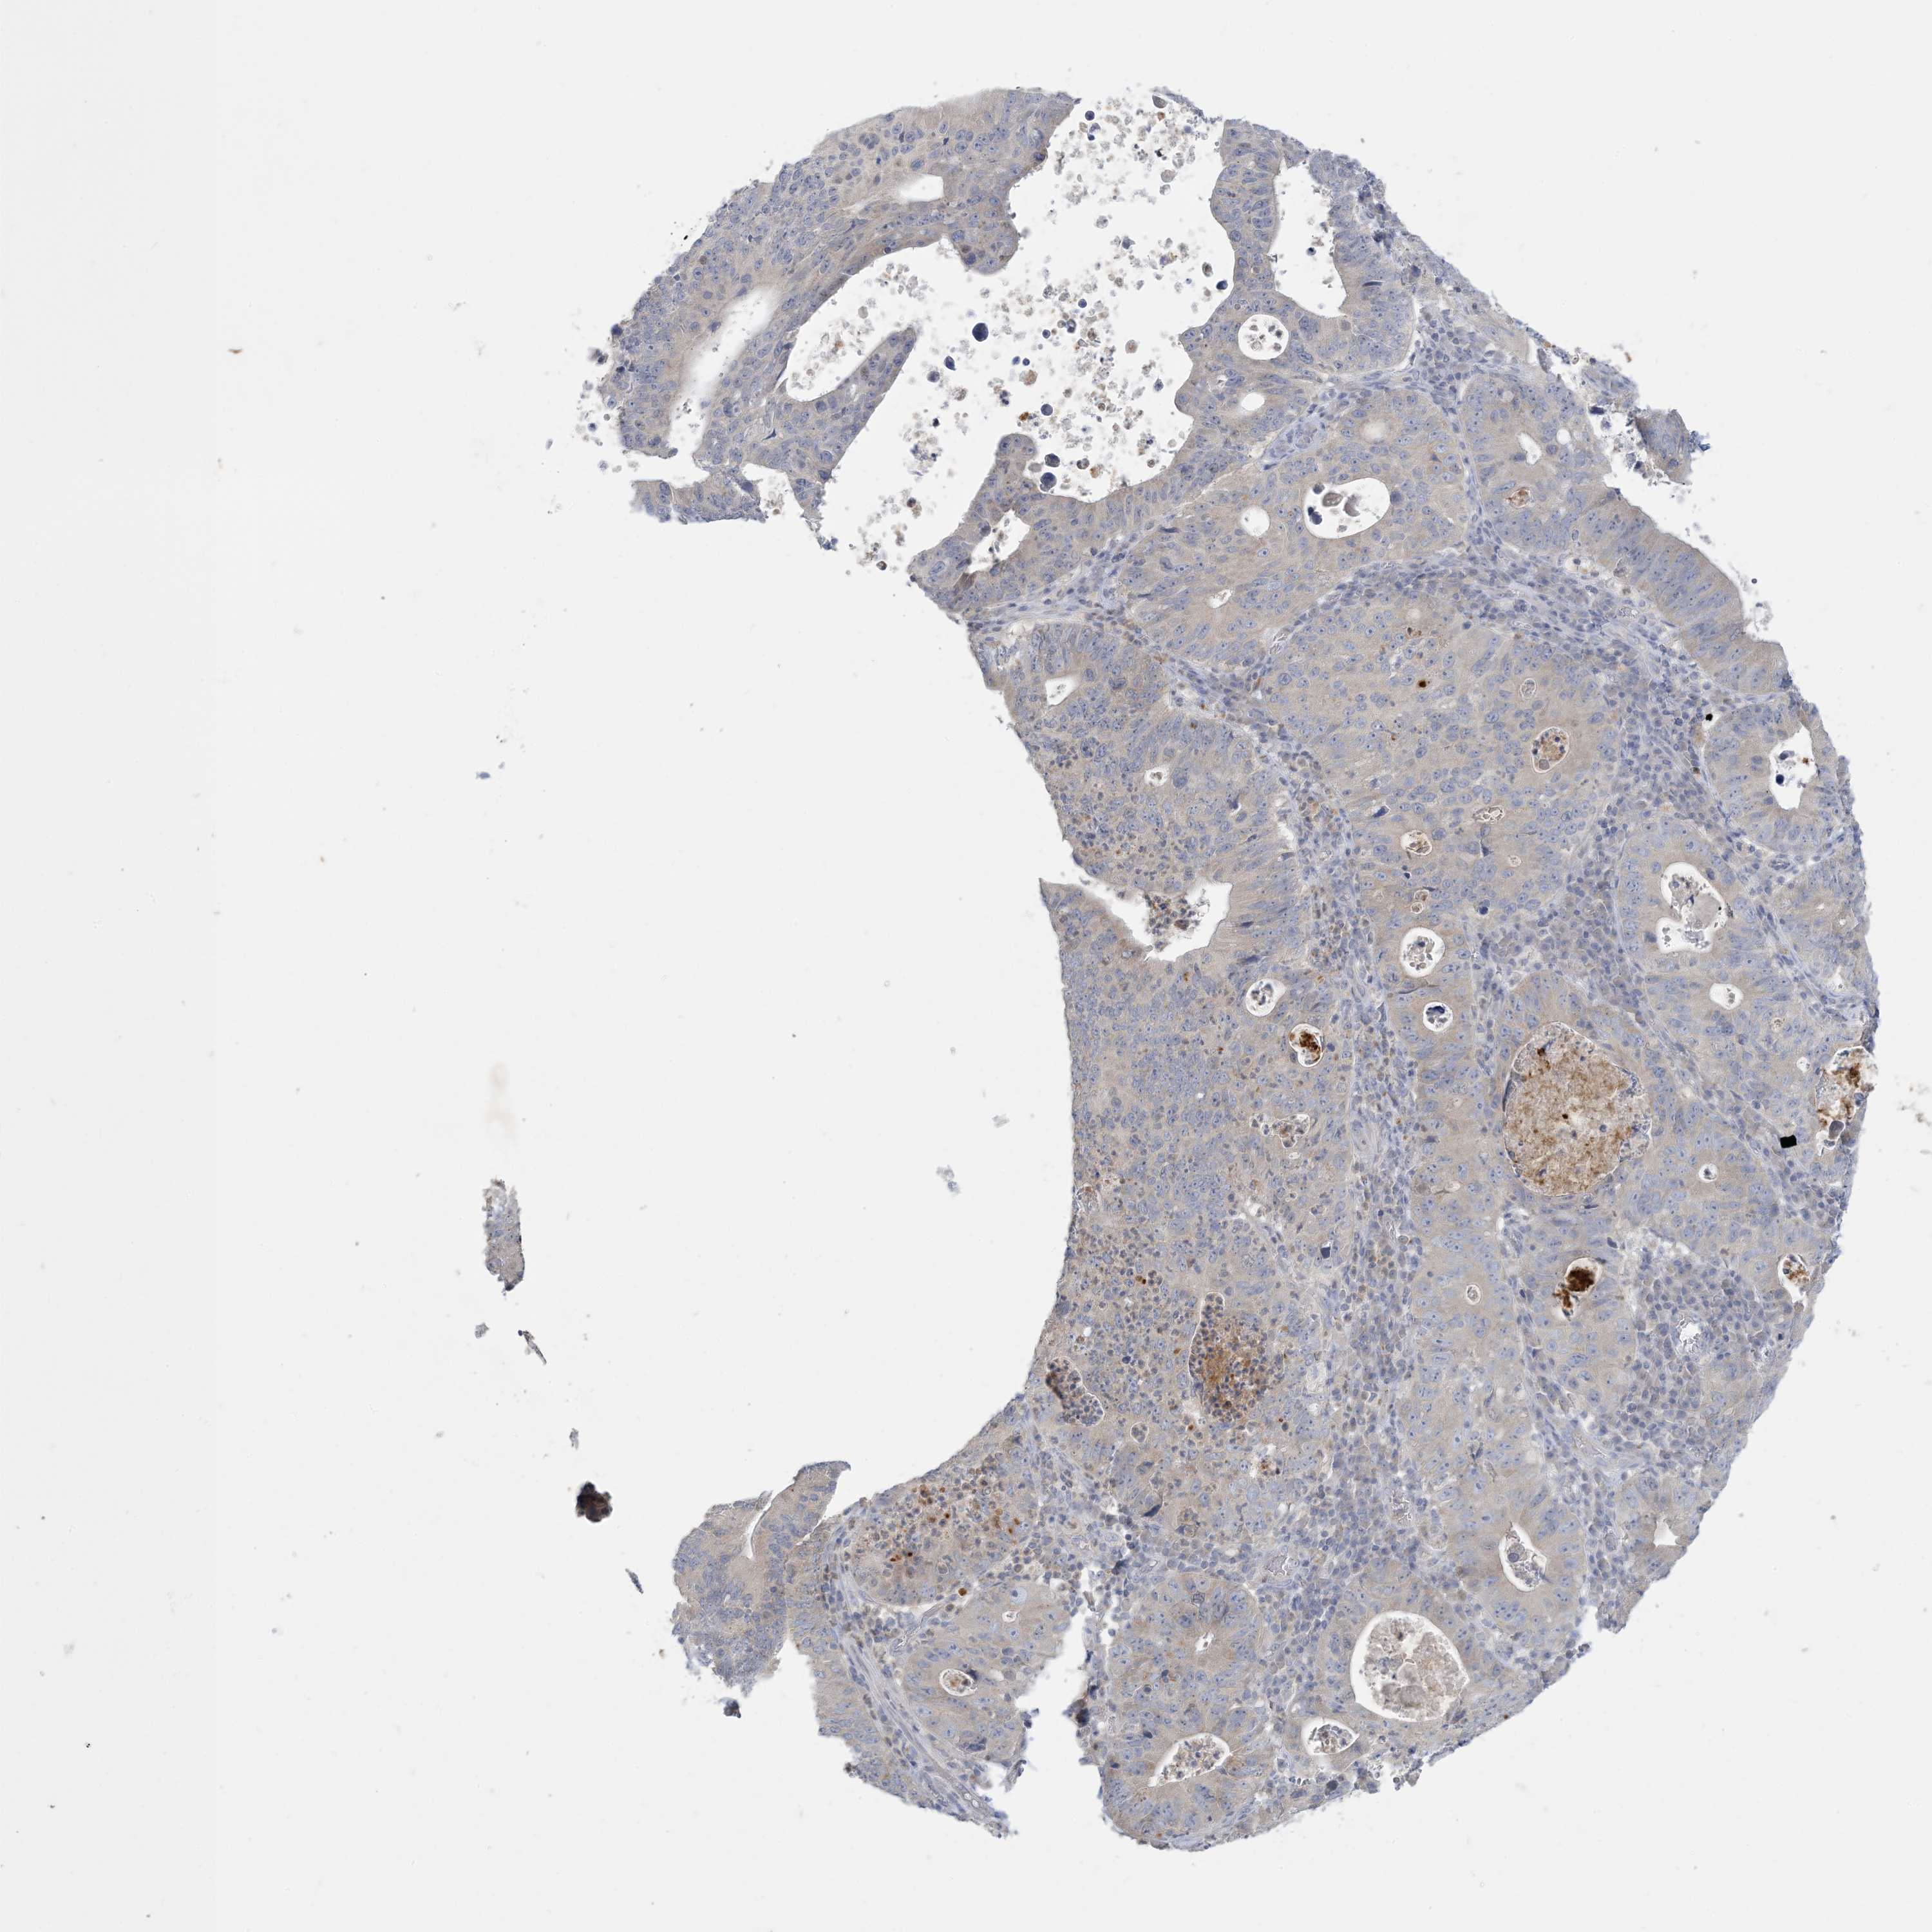

STOMACH CANCER - Protein expressioni

A mouse-over function shows sample information and annotation data. Click on an image to view it in a full screen mode. Samples can be filtered based on level of antibody staining by selecting one or several of the following categories: high, medium, low and not detected. The assay and annotation is described here.

Note that samples used for immunohistochemistry by the Human Protein Atlas do not correspond to samples in the TCGA dataset.

Antibody stainingi

Antibody staining in the annotated cell types in the current human tissue is reported as not detected, low, medium, or high, based on conventional immunohistochemistry profiling in selected tissues. This score is based on the combination of the staining intensity and fraction of stained cells.

Each image is clickable and will lead to virtual microscopy that enables deeper exploration of all samples and also displays staining intensity scores, fraction scores and subcellular localization as well as patient and tissue information for each sample.

Antibody CAB037085

Staining

High

Medium

Low

Not detected

Intensity

Strong

Moderate

Weak

Negative

Quantity

>75%

75%-25%

<25%

None

Location

Nuclear

Cytoplasmic/membranous

Cytoplasmic/membranous,nuclear

Adenocarcinoma, NOS